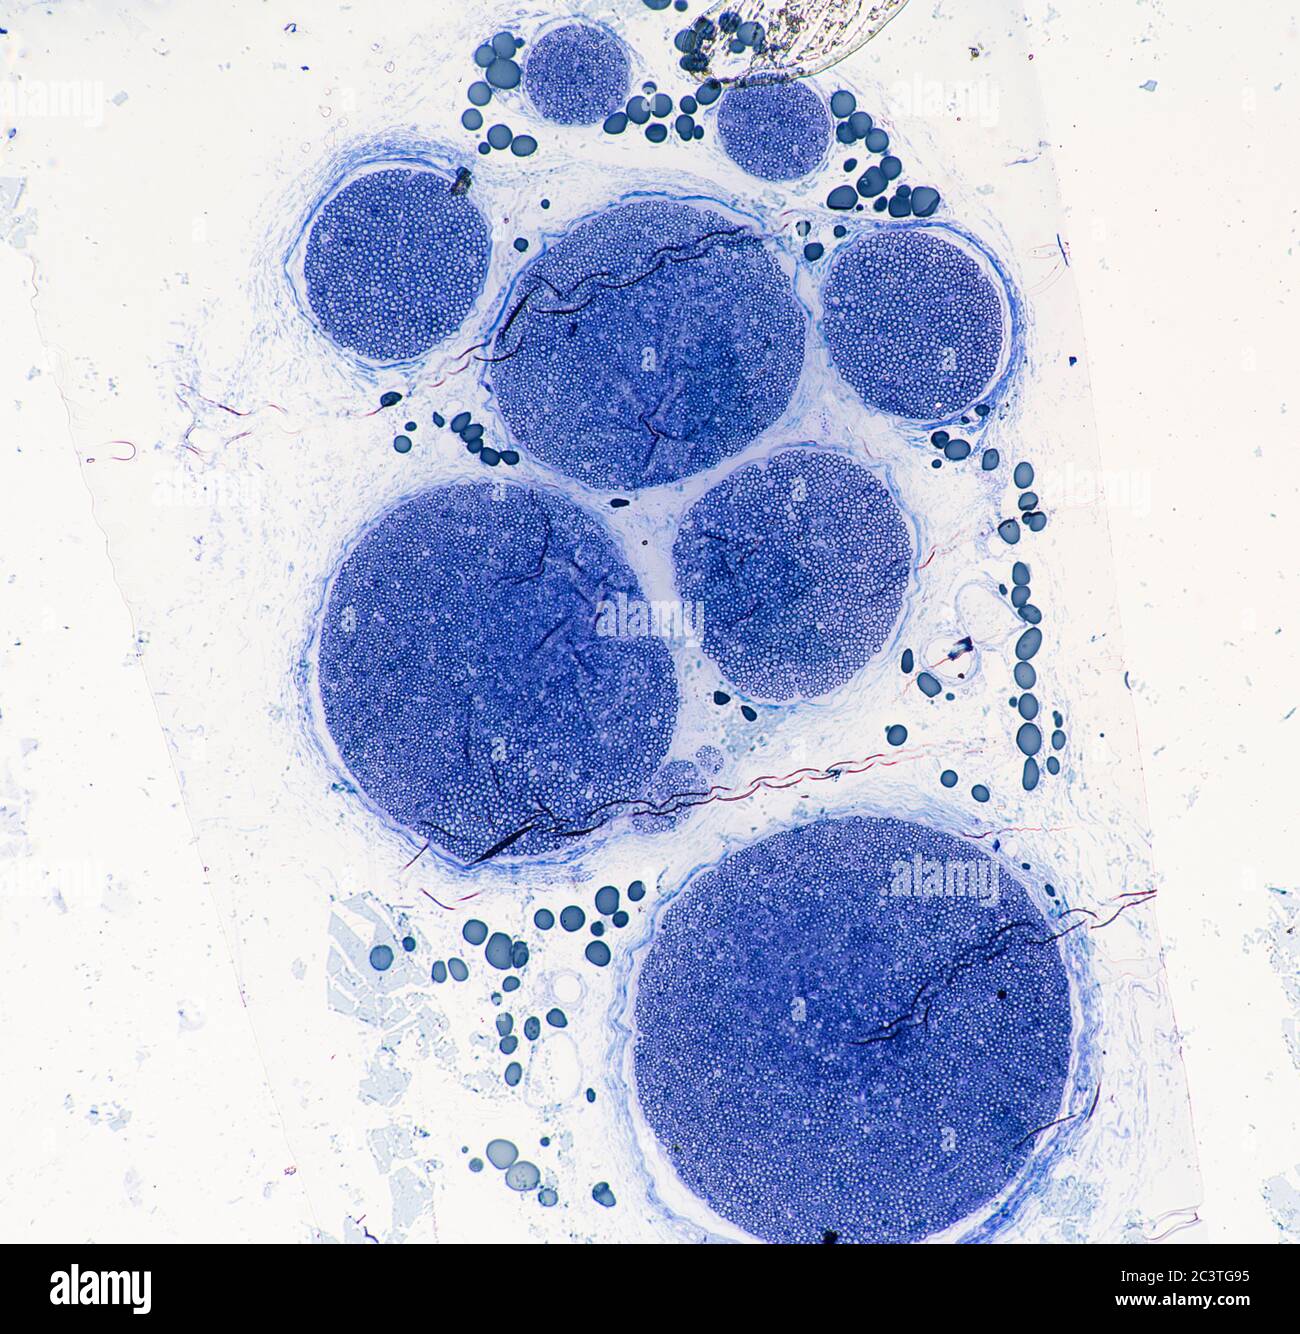

Nerf sciatique de mammifère, coupe transversale, vue au microscope Banque D'Imageshttps://www.alamyimages.fr/image-license-details/?v=1https://www.alamyimages.fr/nerf-sciatique-de-mammifere-coupe-transversale-vue-au-microscope-image363801368.html

Nerf sciatique de mammifère, coupe transversale, vue au microscope Banque D'Imageshttps://www.alamyimages.fr/image-license-details/?v=1https://www.alamyimages.fr/nerf-sciatique-de-mammifere-coupe-transversale-vue-au-microscope-image363801368.htmlRM2C3TGA0–Nerf sciatique de mammifère, coupe transversale, vue au microscope

Nerf sciatique de mammifère, coupe transversale, vue au microscope Banque D'Imageshttps://www.alamyimages.fr/image-license-details/?v=1https://www.alamyimages.fr/nerf-sciatique-de-mammifere-coupe-transversale-vue-au-microscope-image363801345.html

Nerf sciatique de mammifère, coupe transversale, vue au microscope Banque D'Imageshttps://www.alamyimages.fr/image-license-details/?v=1https://www.alamyimages.fr/nerf-sciatique-de-mammifere-coupe-transversale-vue-au-microscope-image363801345.htmlRM2C3TG95–Nerf sciatique de mammifère, coupe transversale, vue au microscope

Nerf sciatique de mammifère, coupe transversale, vue au microscope Banque D'Imageshttps://www.alamyimages.fr/image-license-details/?v=1https://www.alamyimages.fr/nerf-sciatique-de-mammifere-coupe-transversale-vue-au-microscope-image363801326.html

Nerf sciatique de mammifère, coupe transversale, vue au microscope Banque D'Imageshttps://www.alamyimages.fr/image-license-details/?v=1https://www.alamyimages.fr/nerf-sciatique-de-mammifere-coupe-transversale-vue-au-microscope-image363801326.htmlRM2C3TG8E–Nerf sciatique de mammifère, coupe transversale, vue au microscope